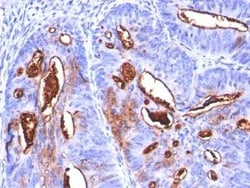

CA19-9/Sialyl Lewis A Monoclonal antibody specifically detects CA19-9/Sialyl Lewis A in Human samples. It is validated for Flow Cytometry, Immunohistochemistry, Immunofluorescence, Immunohistochemistry (Paraffin), Immunofluorescence

| Flow Cytometry 0.5 - 1 ug/million cells in 0.1 ml, Immunohistochemistry, Immunocytochemistry/Immunofluorescence 1-2 ug/ml, Immunohistochemistry-Paraffin 0.5 - 1.0 ug/ml, Immunofluorescence 0.5 - 1.0 ug/ml | |

| Flow Cytometry, Immunohistochemistry, Immunofluorescence, Immunohistochemistry (Paraffin), Immunofluorescence | |